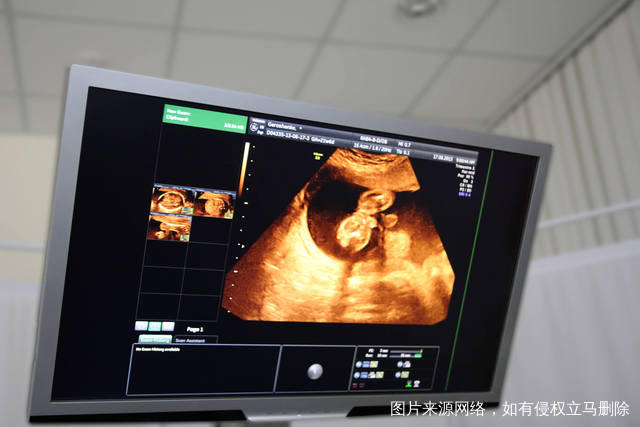

在现实生活当中,如果卵巢里面存在囊肿的话,在怀孕的过程当中可能就会引发流产或者是难产,如果到了中期怀孕的时候会让整个卵巢囊肿和内部的脐带相互扭转到了晚期卵巢囊肿比较大的,还有可能会导致胎位异常分娩的时候有可能就会阻塞产道,从而引起难产,卵巢囊肿这件事情千万不要忽略,如果在孕妇怀孕期间存在卵巢囊肿,一定要到医院检查,结合着自己的情况来进行治疗。